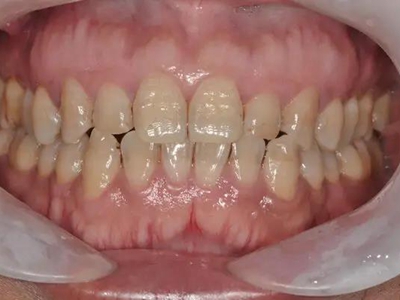

牙釉质发育不全牙上发白图

轻度的牙釉质发育不全患者,牙齿出现色泽和透明度的改变,此时不会影响牙齿的完整形态,也不会导致疼痛不适,仅表现为牙齿上有白色斑点、牙列不齐。

牙釉质发育不全牙齿上有白点图

牙釉质发育不全病情较轻者,只表现为牙齿上有白点,形状不规则,造成牙齿的透明度下降,但牙齿形态依旧完整,也不影响进食。